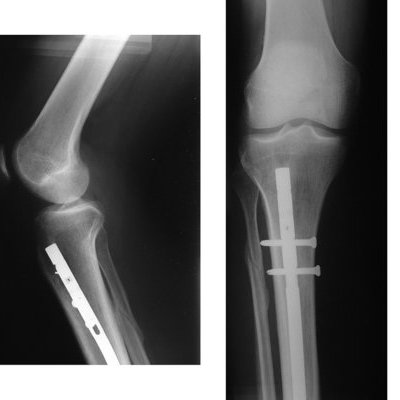

Госкорпорация "Ростех" представила бионический коленный протез "Комета" с микропроцессорным управлением, разработанный "Металлистом". Протез предназначен для пользователей средней и высокой активности.

Встроенный микропроцессор обеспечивает сбор и обработку данных в реальном времени, а нейросеть прогнозирует ритм и рисунок ходьбы. Модуль изготовлен из сверхпрочного российского сплава методом аддитивной печати. Протез способен работать 10 дней от одной зарядки. Проект успешно реализован с участием врачей, реабилитологов и протезистов, превосходя мировые аналоги. Серийное производство запланировано после завершения испытаний в первом квартале 2024 года, сообщает РИА Новости.